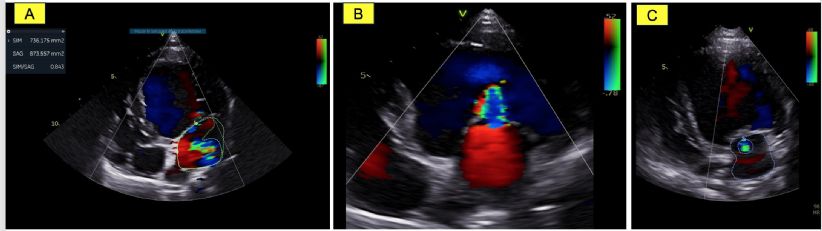

- La valeur très diminuée de la fraction de raccourcissement (FR) égale à 6 %; (valeurs usuelles (VU) 29%) (Figure 1A) ainsi que de la fraction d'éjection (FE) ventriculaire gauche égale à 16% ; (VU 42%) (Figures 2A et 2B) ;

- Une dysfonction systolique nettement améliorée avec une fraction d'éjection normalisée à J0 + 9 mois (Figures 2E et 2F, Tableau 2) malgré la persistance d'une hypokinésie radiale du septum interventriculaire qui contribue au maintien d'une fraction de raccourcissement diminuée mais de façon moindre (FR égale à 23 % à J0 +

9 mois versus 20% à J0+ 3 mois versus 6 % à J0 (Figures 1B, 1C et Tableau 2) ;